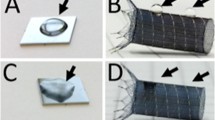

Experimental procedure of the current study. Material preparation in the form of stent extraction, coating and reinsertion (a). In vivo analysis consisting of 3D CT angio scans (b), coupled with 3D segmentation (c) and volumetric analysis over time (d). In vitro experiments utilizing blood sampling and chandler loop models coupled with ELISA and Multiplate analysis kits for blood marker analysis (e). Analysis of the coatings integrity after implantation with SEM (f).